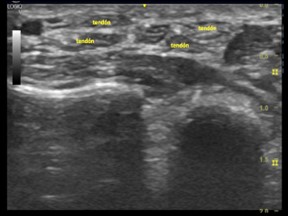

Imagen ecográfica 2.1 Eje longitudinal y transversal de los tendones del músculo flexor de los dedos.

Los tendones poseen gran anisotropía. Ósea los tendones tienen mayor  variabilidad de la ecogenicidad al modificar el ángulo de isonación. Además en comparación con los nervios el tendón posee menos ecos paralelos delgados y densamente empaquetados, es mas circular que oval  y mas móvil durante maniobras de flexión y extensión.